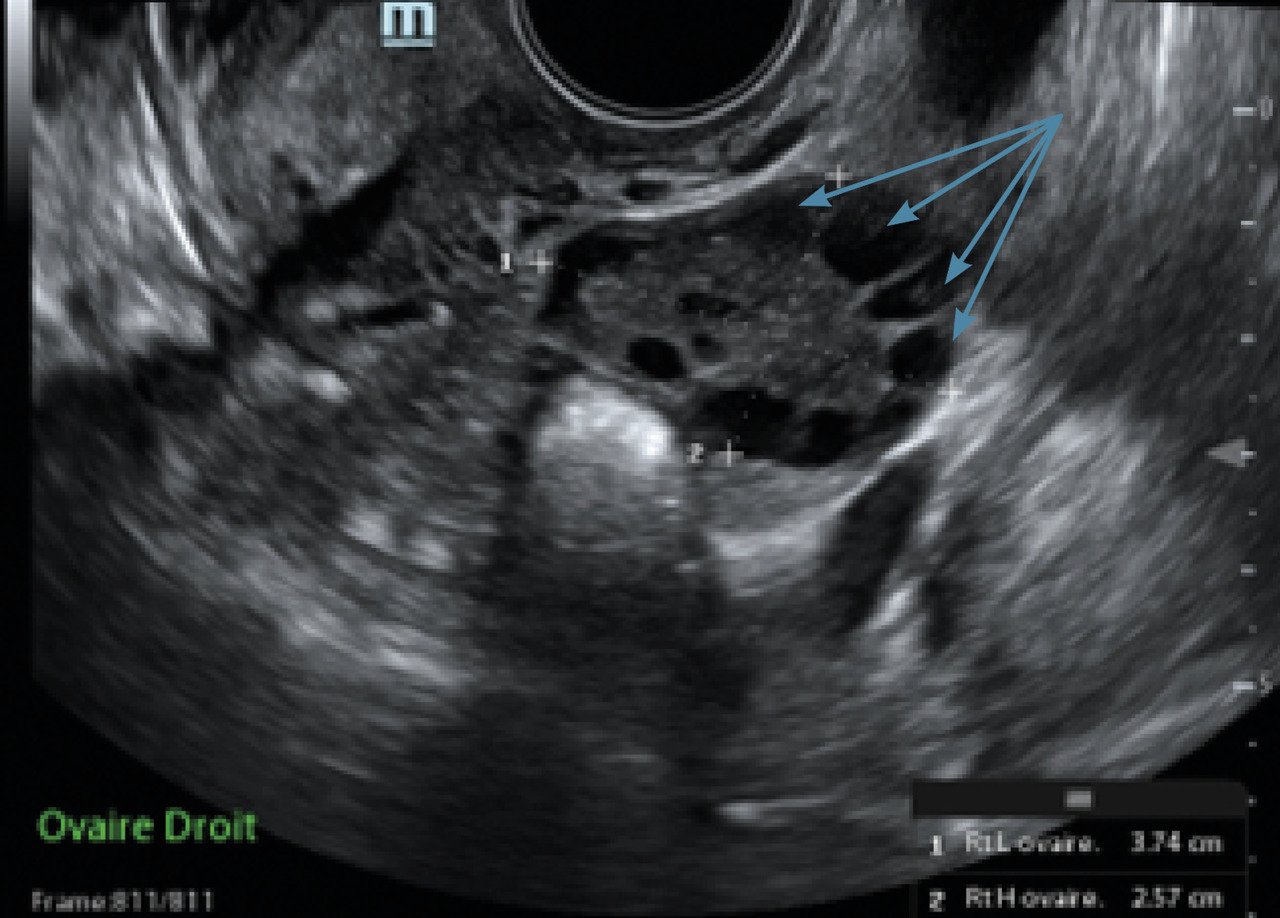

L’immense majorité des cas d’aménorrhée secondaire est due à un SOPK (fig. 3 et 4).

• un compte des follicules antraux (CFA) supérieur ou égal à 20 par ovaire (ou un volume ovarien augmenté, supérieur à 10 mL).

Le CFA correspond au compte des follicules antraux mesurant 2 à 9 mm à l’échographie par voie vaginale. Le dosage de l’AMH peut être utile car il est corrélé au nombre de follicules antraux.

Il n’est pas recommandé de réaliser une échographie pelvienne avec CFA pour le diagnostic de syndrome des ovaires polykystiques moins de huit années suivant la ménarche, en raison de la fréquence très élevée d’un aspect multifolliculaire des ovaires chez les adolescentes.